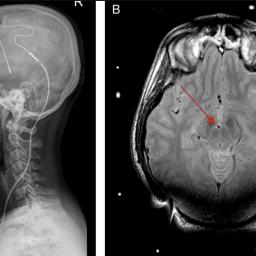

|  | by David Pescovitz on  (#3P7YB) Deep brain stimulators -- pacemaker-like implants that deliver electrical impulses to specific regions in the brain -- are common treatments for Parkinson's and other neurological disorders. It's known that strong electromagnetic fields from the likes of ham radio antennae and arc welders can damage the devices. Now, researchers report the case of a 66-year-old woman whose deep brain stimulator was knocked out when lightning hit her apartment. Fortunately, the lightning shut off the device without damaging her brain. “The patient was not charging the battery of her IPG (implantable pulse generator) during the event, and the recharger for the IPG was disconnected from the power supply during the storm," the researchers wrote. "The recharger and IPG were therefore not destroyed. The patient realized that something was wrong only 1 hour after the storm subsided, when the dystonic tremor in her neck reappeared.â€"Lightning may pose a danger to patients receiving deep brain stimulation: case report" (Journal of Neuroscience via Mysterious Universe) |